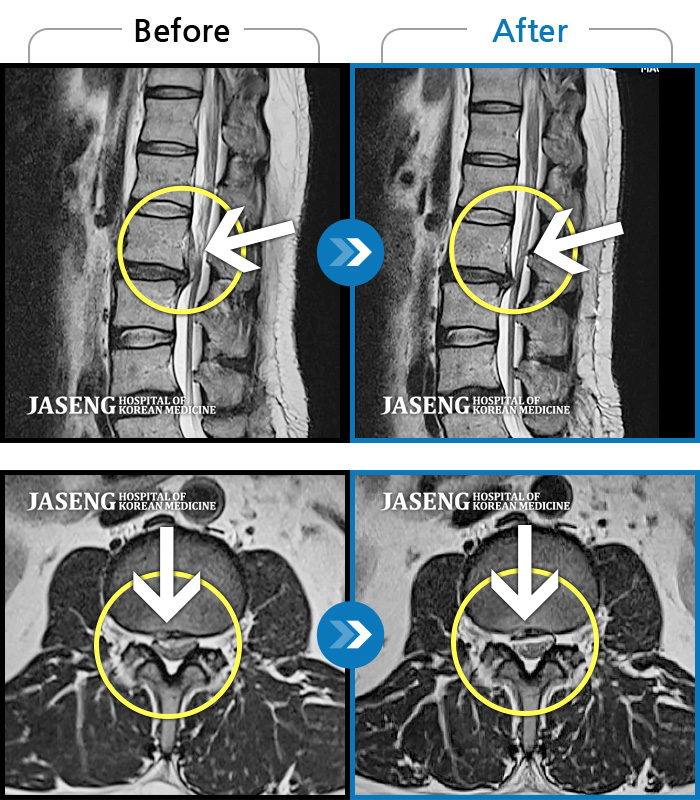

목디스크

분당 · 이효은 원장

목 통증 및 우측 팔 통증으로 위로 들 수 없는 상태

촬영시기

2017.01.05 ~ 2017.08.04

2017.08.21